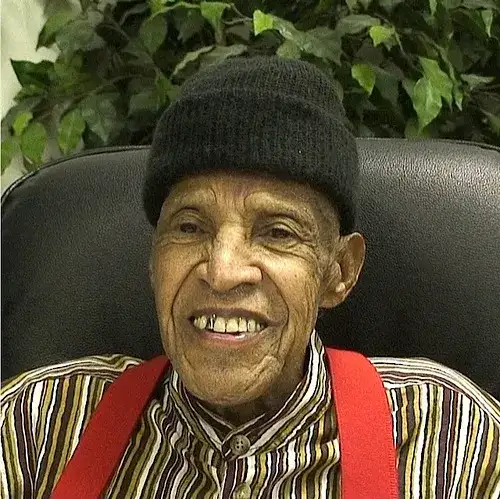

让我们回到文章开头的雅科夫。他在七岁那年接受头癣治疗后,头发虽然重新长了出来,但头顶留下了一块永久的秃斑。青春期时,他开始频繁地感到疲倦和头晕,但医生们找不到原因。1985年,三十八岁的雅科夫被诊断出甲状腺癌,接受了甲状腺切除手术。手术成功了,但他必须终身服用甲状腺激素替代药物。

1994年,当赔偿法案通过时,雅科夫试图申请赔偿。但他发现自己无法提供医疗记录——当年的移民接收中心早已关闭,档案不知所终。他花了数年时间奔波于各种政府办公室,最终在一位社工的帮助下,找到了一份模糊的登记表,证明他确实在1954年接受过头癣治疗。2010年,雅科夫终于获得了每月数百谢克尔的赔偿金。他说,钱不多,但至少是一种承认。

雅科夫的故事只是成千上万个类似故事中的一个。每一个数字背后,都是一个被改变的人生,一个被辜负的希望,一个被遗忘的灵魂。当我们在今天回顾这段历史时,我们不仅是在追究过去的责任,更是在为未来建立警示。因为只要有任何群体被认为是"可牺牲的",这样的悲剧就可能重演。